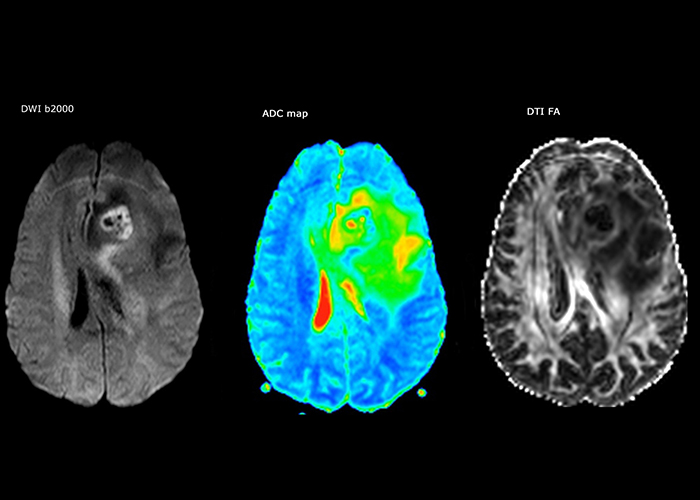

“The biggest challenges are properly characterizing the lesion and giving the surgeon all the information needed, such as the location of vessels and functional areas. Sometimes a very comprehensive exam is necessary, such as when a mass has been discovered at another hospital after which the patient is referred to us. We then do both lesion characterization and preoperative imaging in one exam, so both morphologic and functional assessment. For morphologic assessment we will use pre- and post-contrast T1-weighted imaging, FLAIR to assess infiltration, and diffusion. For functional characterization we will perform perfusion, spectroscopy, and susceptibility weighted imaging to look for micro vessels or micro hemorrhage inside the lesion[4]. For preoperative imaging we perform specific morphologic imaging that is compatible with the navigation system; depending on the location of the tumor, we would do fMRI or DTI.”

The first challenge in MRI of stroke is speed. The patient typically arrives from an ambulance in the MRI preparation room and the installation is done on a separate dock outside the scanner room. “The venous access is placed during the neurological examination. If the delay from the first symptoms allows the patient to receive thrombolysis we do a very fast examination that typically lasts about 11 minutes including the pre-scans. In the case of transient ischemic stroke we usually add ASL perfusion because in some symptoms with negative diffusion, ASL sometimes indicates a vascular origin.”

“Ingenia provides great flexibility in the parameters setting. We can tune a sequence the way we want,” says Dr. Savatovsky. “For example, in a stroke exam we use a FLAIR sequence of about two minutes instead of the four-minute FLAIR we use for MS. The diffusion is 30 seconds, the T2*-weighted scan is 30 seconds, the angiography scan time is less than one minute. Ingenia is a great scanner in that situation; even with these fast sequences we can achieve good images with good SNR. When the first sequence tells us that it’s not an ischemic stroke but a hemorrhagic stroke, we may switch to a time-resolved angiography to look for vascular malformations and venous thrombosis.

“Every center is different, but for me the ideal protocol for stroke includes diffusion weighted imaging, FLAIR, and fast susceptibility imaging,” says Dr. Savatovsky. “Our fast susceptibility weighted imaging takes 50 seconds, so it’s as fast as T2*-weighted imaging. It visualizes hemorrhage but also the clots. We also do 3D MR angiography that provides information on cervical and brain vessels. If the patient does not need immediate treatment, or if additional information is needed to decide on treatment, we might also add perfusion imaging and post-contrast T1-weighted imaging.”